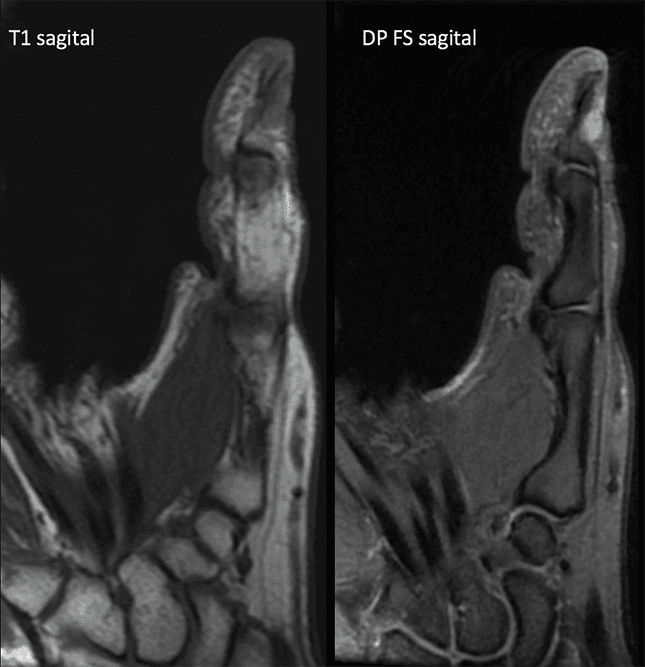

Paciente do sexo feminino, 47 anos, com lesão nodular dolorosa subungueal no I dedo há meses. Relata aumento da sensibilidade nesta região, especialmente no frio.

Imagens